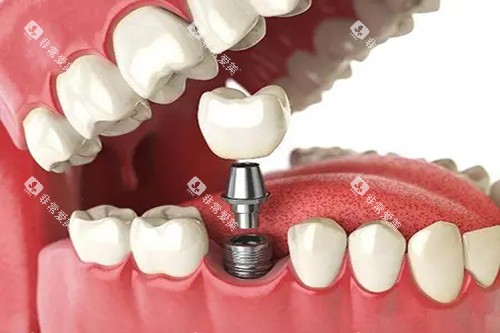

例如,在牙齿种植领域,医生们能够根据患者的口腔状况和身体条件,制定个性化的种植方案,确保种植结果的稳定性和美观性。